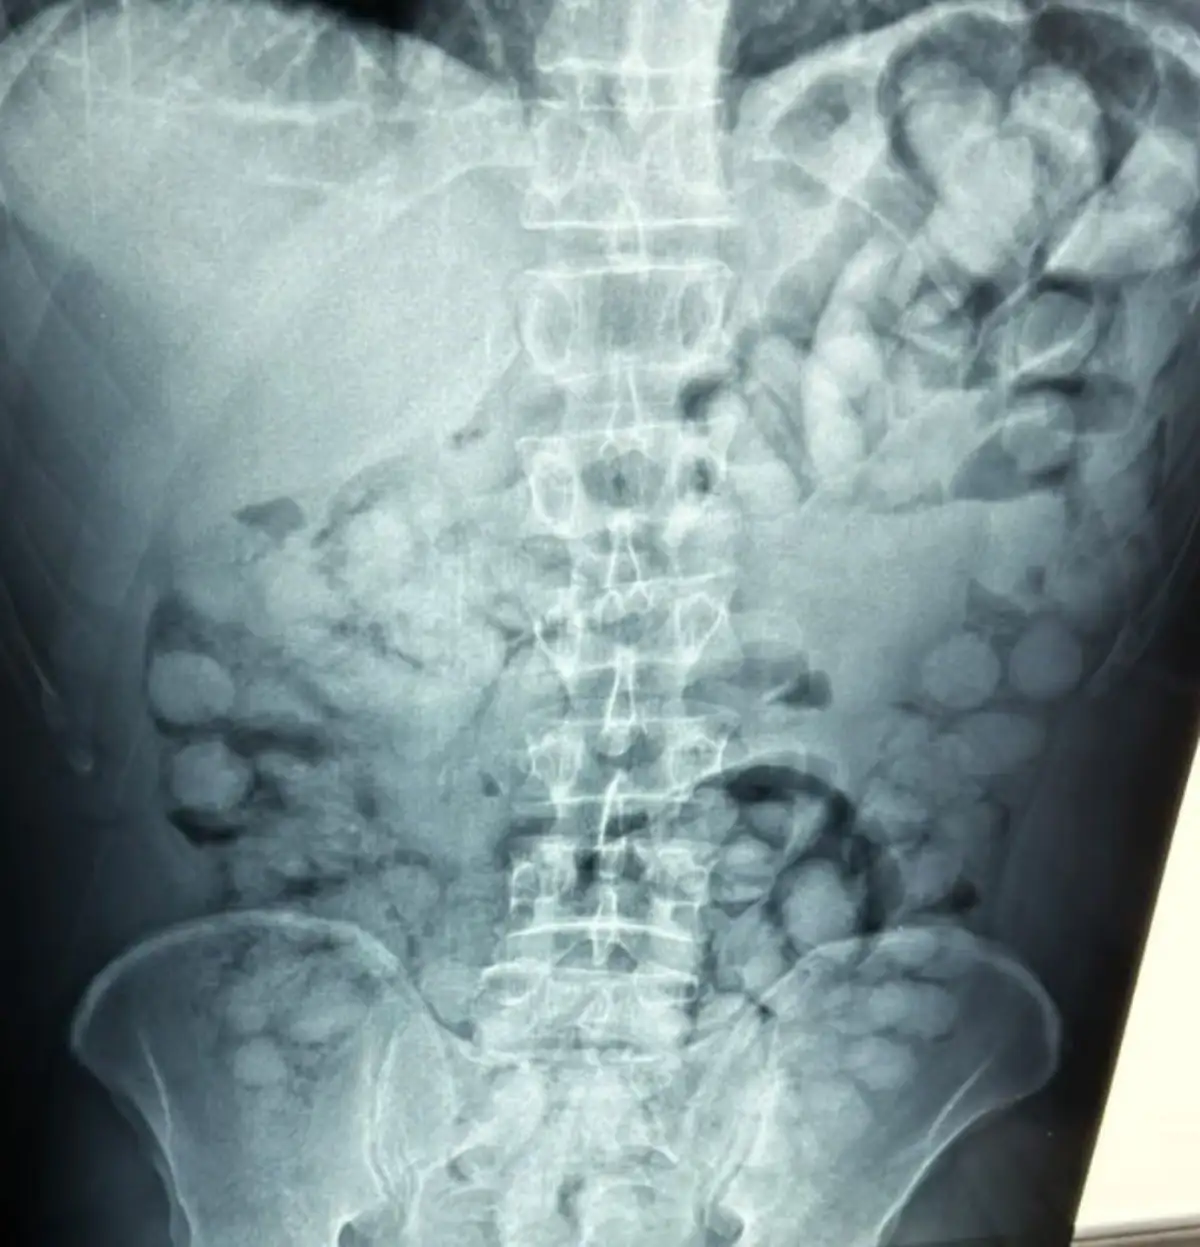

Σύμφωνα με την ΕΛΑΣ, ο άνδρας έφτασε στην Αθήνα, μέσω Παρισιού και στον έλεγχο που διενεργήθηκε, διαπιστώθηκε ότι είχε καταπιεί περίπου 100 «αυγουλάκια» κοκαΐνης.